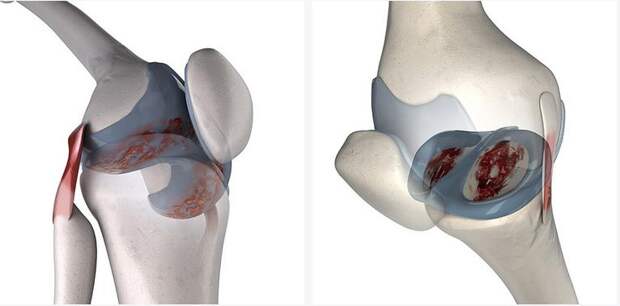

Чаще всего повреждения в тканях происходят на фоне возрастных изменений, а также из-за травм (как правило, спортивных). В этом случае люди начинают испытывать довольно сильные боли в пораженной области, им становится сложнее двигать верхними и нижними конечностями. Если в такой ситуации человеку не оказывается специализированная помощь, то это может привести к еще большему изнашиванию суставов. Из-за этого на руки и ноги будут оказываться слишком сильные нагрузки. Без вспомогательных средств регенерация хрящевой ткани становится невозможной и человек рискует заполучить более серьезные осложнения.

Особенности восстановления

В первую очередь стоит сказать, что хрящевая ткань являются довольно хрупкой субстанцией, которую можно без проблем повредить и нанести организму вред. Если человек неправильно будет распределять нагрузку или повышать ее, то это только ухудшит его состояние. Именно поэтому не стоит заниматься самолечением, а лучше обратиться к специалисту.

Как правило, для того, чтобы восстановить нормальную хрящевую ткань в суставах, необходимо принимать хондопротекторы. Наиболее эффективными данные средства будут в том случае, если человек обратился за помощью на начальной стадии заболевания суставов. Если речь идет о запущенной форме недуга, то, говоря о том, можно ли восстановить хрящевую ткань в суставах в этом случае, вероятнее всего ответ будет отрицательным. В такой ситуации способно помочь только хирургическое вмешательство. При помощи медикаментозной терапии подобные проблемы будет решить достаточно сложно. Поэтому не стоит дотягивать до последнего и прибегать к более серьезным процедурам.